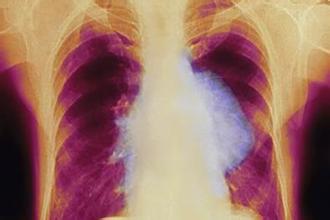

胸水往往是肺癌恶化到一定程度后出现的并发症,治疗上需要针对原发病灶的同时,还要对胸水进行对症治疗,才能做到标本兼治。

我的一位患者71岁老人,18年5月无明显诱因出现右侧胸痛,持续4天后入院检查发现肺癌伴胸水,行化疗并抽胸水治疗,症状得到缓解,但随后胸水复发,且化疗副作用明显,综合考虑后转中医治疗。

服药7剂后复诊,患者诉胸痛有所缓解、咳嗽有所减轻,遂开原方继服;再1月后,胸闷症状缓解近一半,睡眠也有所改善,能安稳睡个5、6小时左右;治疗3个月后复查,肿瘤稍有缩小,胸水已消退,且无复发,遂继服用中药治疗,至今也已有3年余。